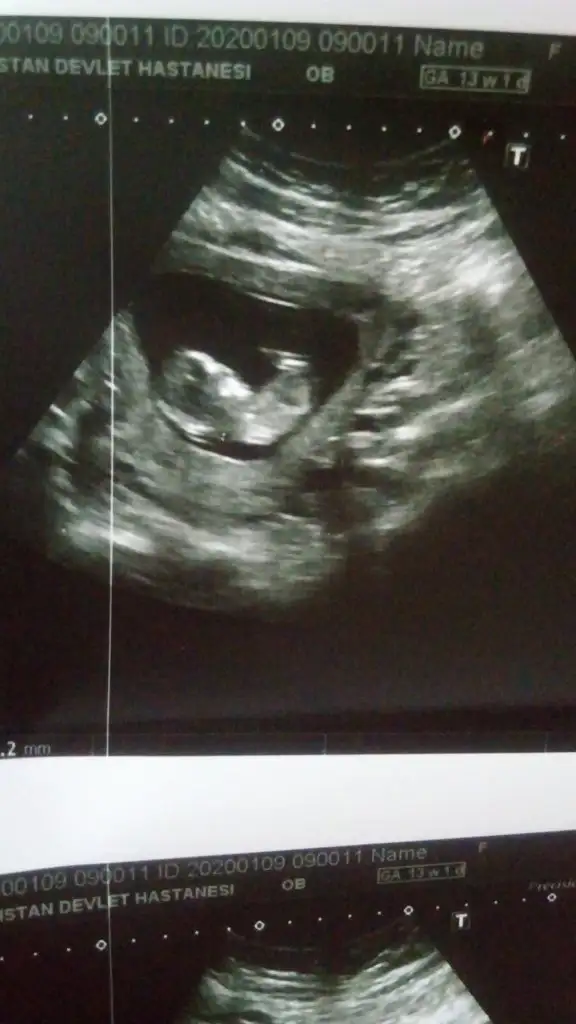

9 haftalık degil ya 5+ yada 6+ olmalı kese içinEki Görüntüle 2574903 bu da karından bakılan 9 haftalık

Daha önce ne dedim bilmiyorum burada nub paralel görünüyor kız gibi 12+ usg olursa paylaşınEki Görüntüle 2574907 Eki Görüntüle 2574908 Eki Görüntüle 2574909 Canım 11+1ız sabah dayanamadık doktora gıttık.cınsıyetı bellı degl ama eşim cok merak edıyor sor bakalım dıyor nub a göre neymıs cınsıyetı dıyebıze tekrar bakarsan cok sevınırım

Daha önce erkek demıstınız ama o zaman 10 haftalıktı.12.haftayı paylaşacağım cok teşekkürlerDaha önce ne dedim bilmiyorum burada nub paralel görünüyor kız gibi 12+ usg olursa paylaşın

11 yada 12 hafta tekrar paylaşırsınız şimdilik erkek ama 12 hafta tahminimi onaylarız

Erkek olduğunu tahmin ediyorum